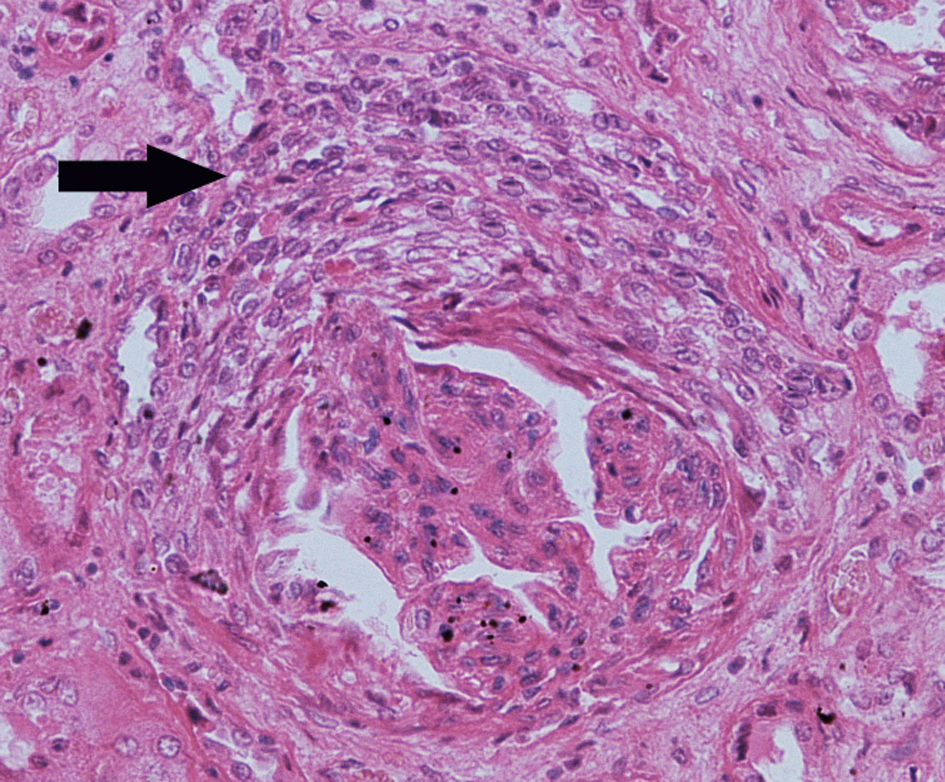

2.Crescentic glomerulonephritis